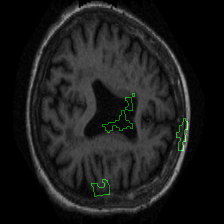

Figure 1 presents attribution maps generated using PWIG for a selection of MRI scans across all four diagnostic categories. The highlighted regions (in green) correspond to the areas that contributed most significantly to the model’s decision. Notably, we observe consistent emphasis on anatomical structures that align with clinical markers of dementia, including cortical and subcortical regions. For instance, in the moderate and mild dementia examples, the model focuses on regions exhibiting visible atrophy or abnormal morphology. In contrast, attribution maps for non-demented subjects appear more diffuse and less concentrated, reflecting the model’s detection of normal anatomical patterns.

The results in Figure 1 demonstrate that PWIG can effectively produce interpretable and clinically meaningful explanations for model predictions in medical imaging tasks.

Figure 1: PWIG attribution maps across dementia categories using the OASIS-1 dataset. Green overlays indicate regions with the highest attribution scores.